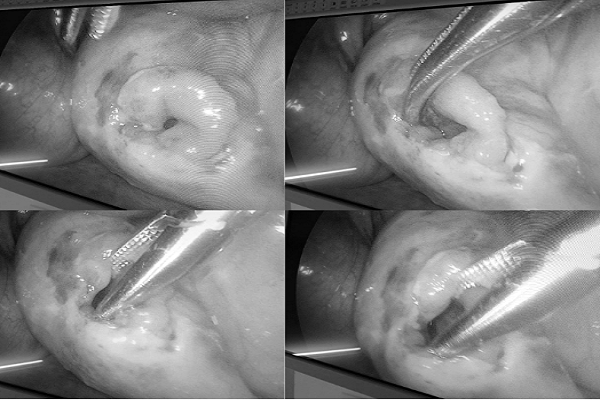

Qua nội soi phát hiện lổ thủng trên ruột của bệnh nhân - Ảnh: BVCC

ThS-BS Lê Hữu Đăng (Khoa Ngoại Tổng hợp) – phẫu thuật viên chính của ca mổ – cho biết ca phẫu thuật đối mặt với nhiều thách thức. Bác sĩ Đăng chia sẻ: “Khi vào ổ bụng, chúng tôi ghi nhận một lỗ vỡ ruột kích thước khoảng 2 cm, dịch tiêu hóa đang tràn ra ngoài. Các quai ruột chướng nhiều, không gian thao tác rất hạn chế vì ổ bụng trẻ nhỏ”.

Ê-kíp tiến hành cắt lọc tổ chức dập nát và khâu phục hồi lỗ thủng hoàn toàn bằng phương pháp nội soi. Đồng thời, toàn bộ ổ bụng được kiểm tra kỹ lưỡng để tránh bỏ sót tổn thương các tạng khác – điều đặc biệt quan trọng trong chấn thương bụng do tai nạn giao thông.